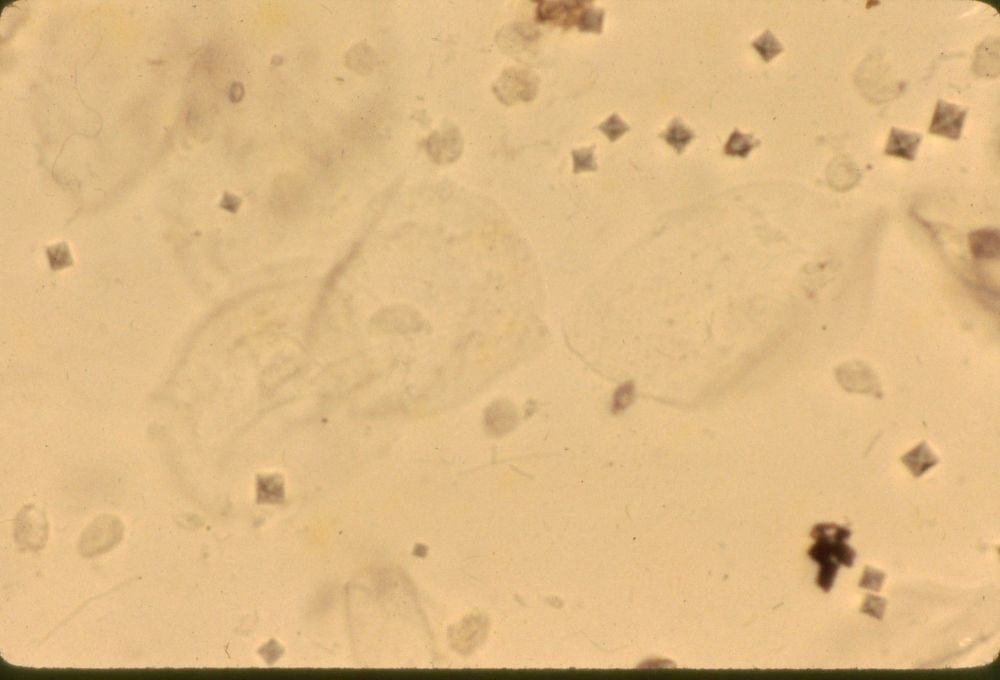

Image:

Cast (image/jpeg)

Cast |